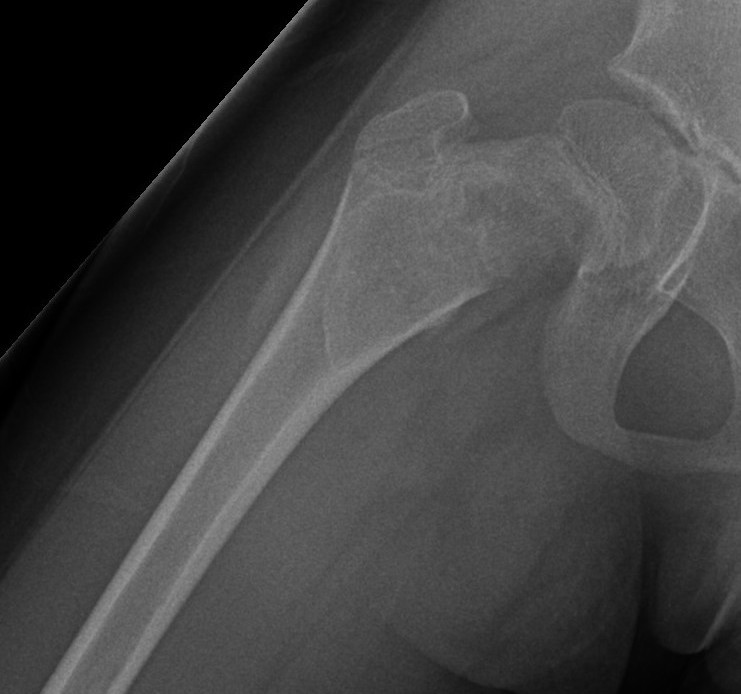

Coxa vara and Shepherd's Crook deformity of proximal femur

- Shepherd's Crook - anterior bowing of femur

- secondary leg length discrepancy

- pain, difficulty walking

Proximal femur coxa vara and shepherds crook deformity

- 209 patients with FD of the proximal femur

- 12% developed osteoarthritis

- 10 hips in 9 patients with 6 year follow up

- osteotomy to correct coxa vara

- proximal femoral allograft used +/- strut allograft

- one revision due to poor bone stock and femoral implant subsidence